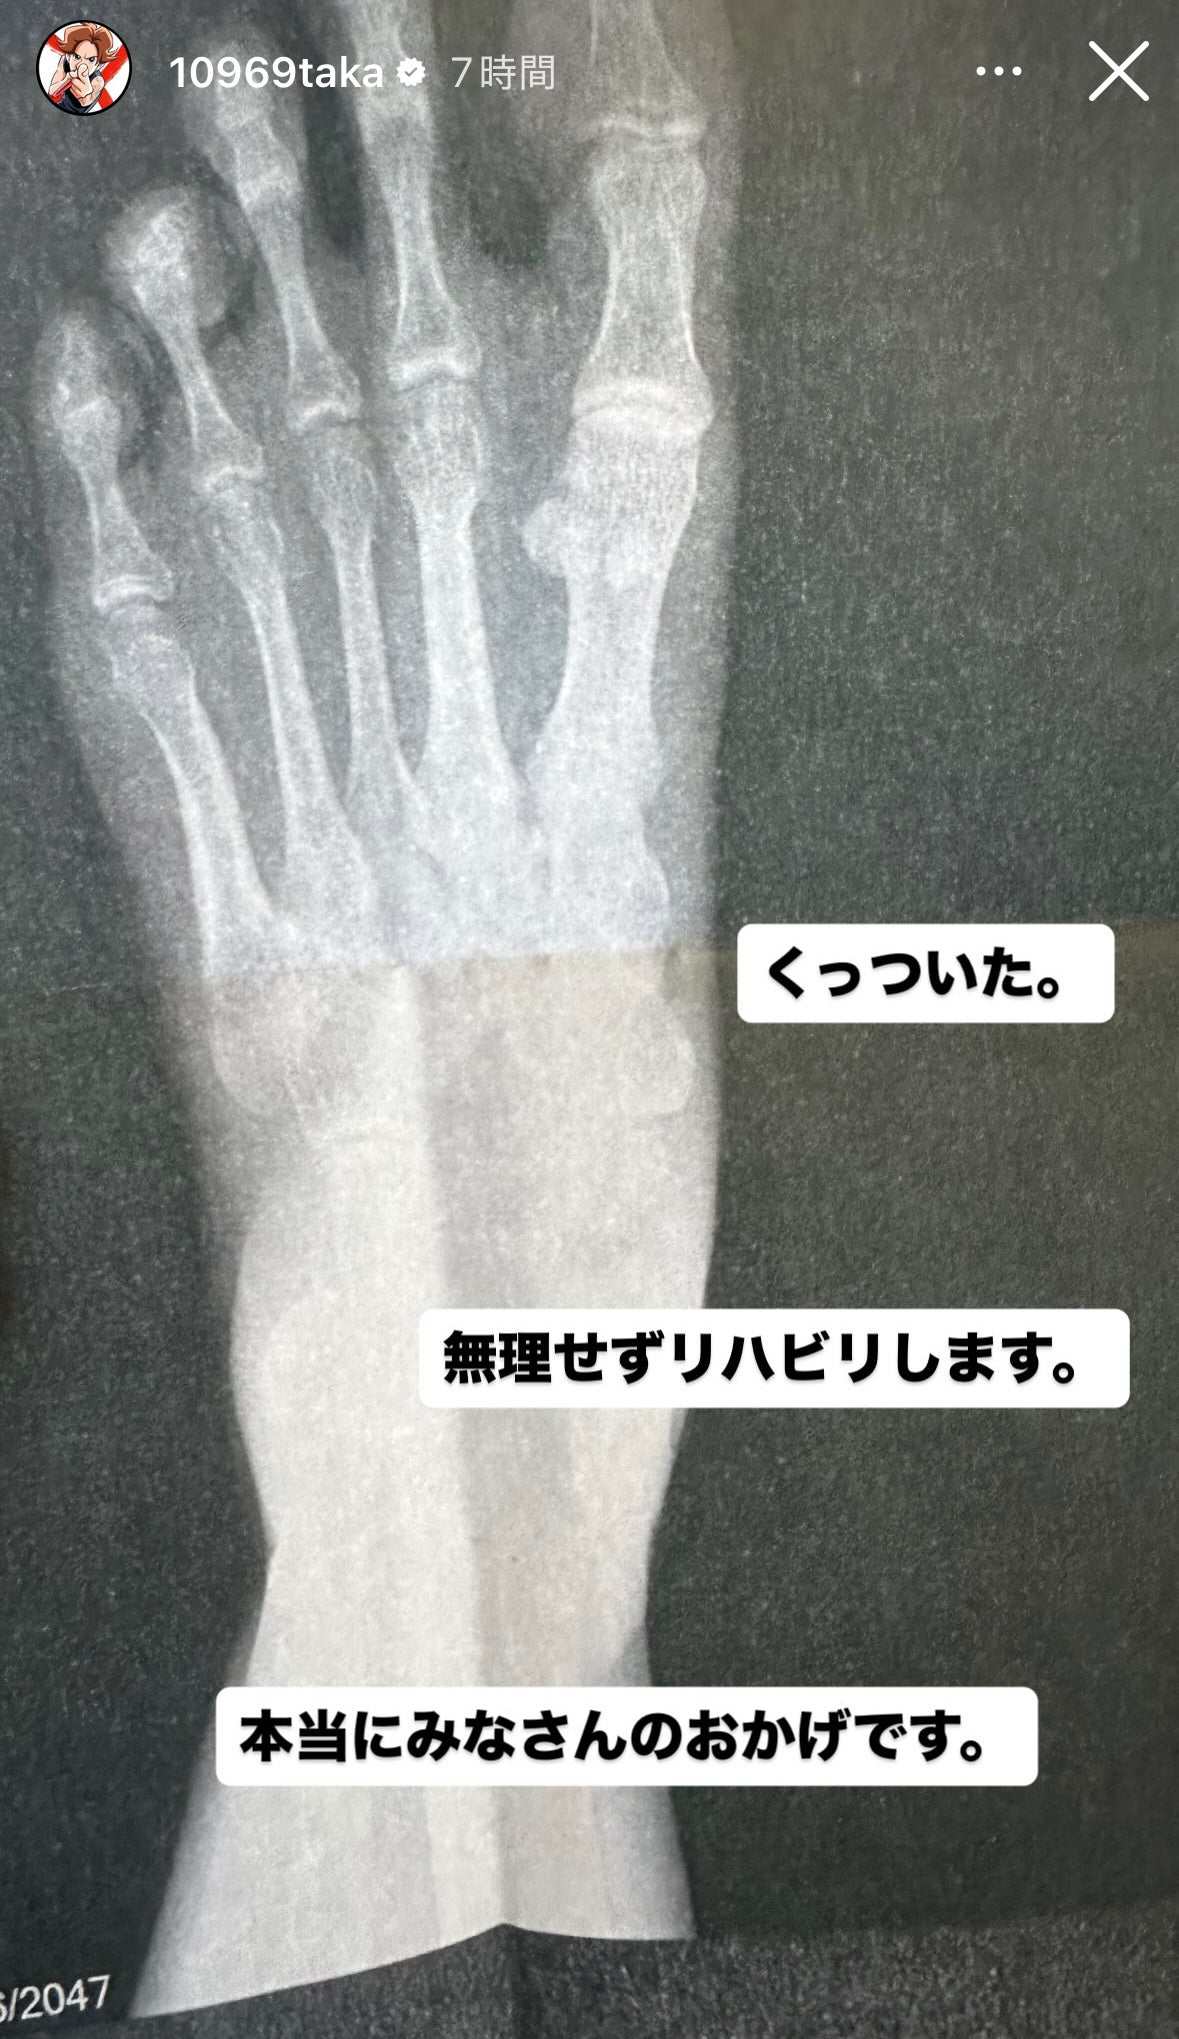

3. ワンオクTaka、骨折していた左足小指の経過報告「無理せずリハビリします」レントゲン写真も公開